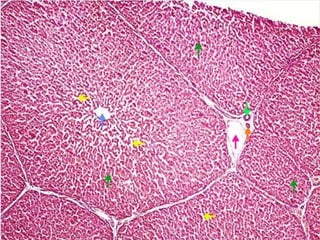

Aparato digestivo tubular

 Mucosa

 Submucosa

 Muscular

 Serosa

Mucosa

 Formada por:

1. Membrana epitelial superficial

2. Lámina propia

3. Muscularis mucosae

 Contiene vellosidades y criptas que incrementan la

capacidad de absorción y secreción

 Capilares sanguíneos que absorven las sustancias

alimenticias

 Producen IgA

Submucosa

 Tejido conectivo areolar grueso con fibras elásticas muy

notables

 Permite la movilidad de la mucosa y contiene plexos de

vasos sanguíneos y nervios mayores con algunas células

ganglionares

 Los nervios están formados por fibras posganglionares

amielínicas del simpático. Con algunas fibras

preganglionares del parasimpático procedentes del nervio

vago

 Las fibras posganglionares inervan la muscularis mucosae

y las glándulas mucosas

 Plexo submucoso de Meissner

Muscular externa

 Se dispone en dos capas:

 Circular interna: Estrecha la luz

 Longitudinal externa: Acorta el intestino

 Entre las dos hay un plexo vascular y un plexo nervioso

 Plexo mientérico de Auerbach: en su mayor parte es

parasimpático y produce las ondas peristálticas

 Lentas

 Rápidas

Serosa (adventicia)

 Tejido conectivo areolar relativamente denso y elástico

 En algunas regiones está cubierta por peritóneo y se la

denomina serosa